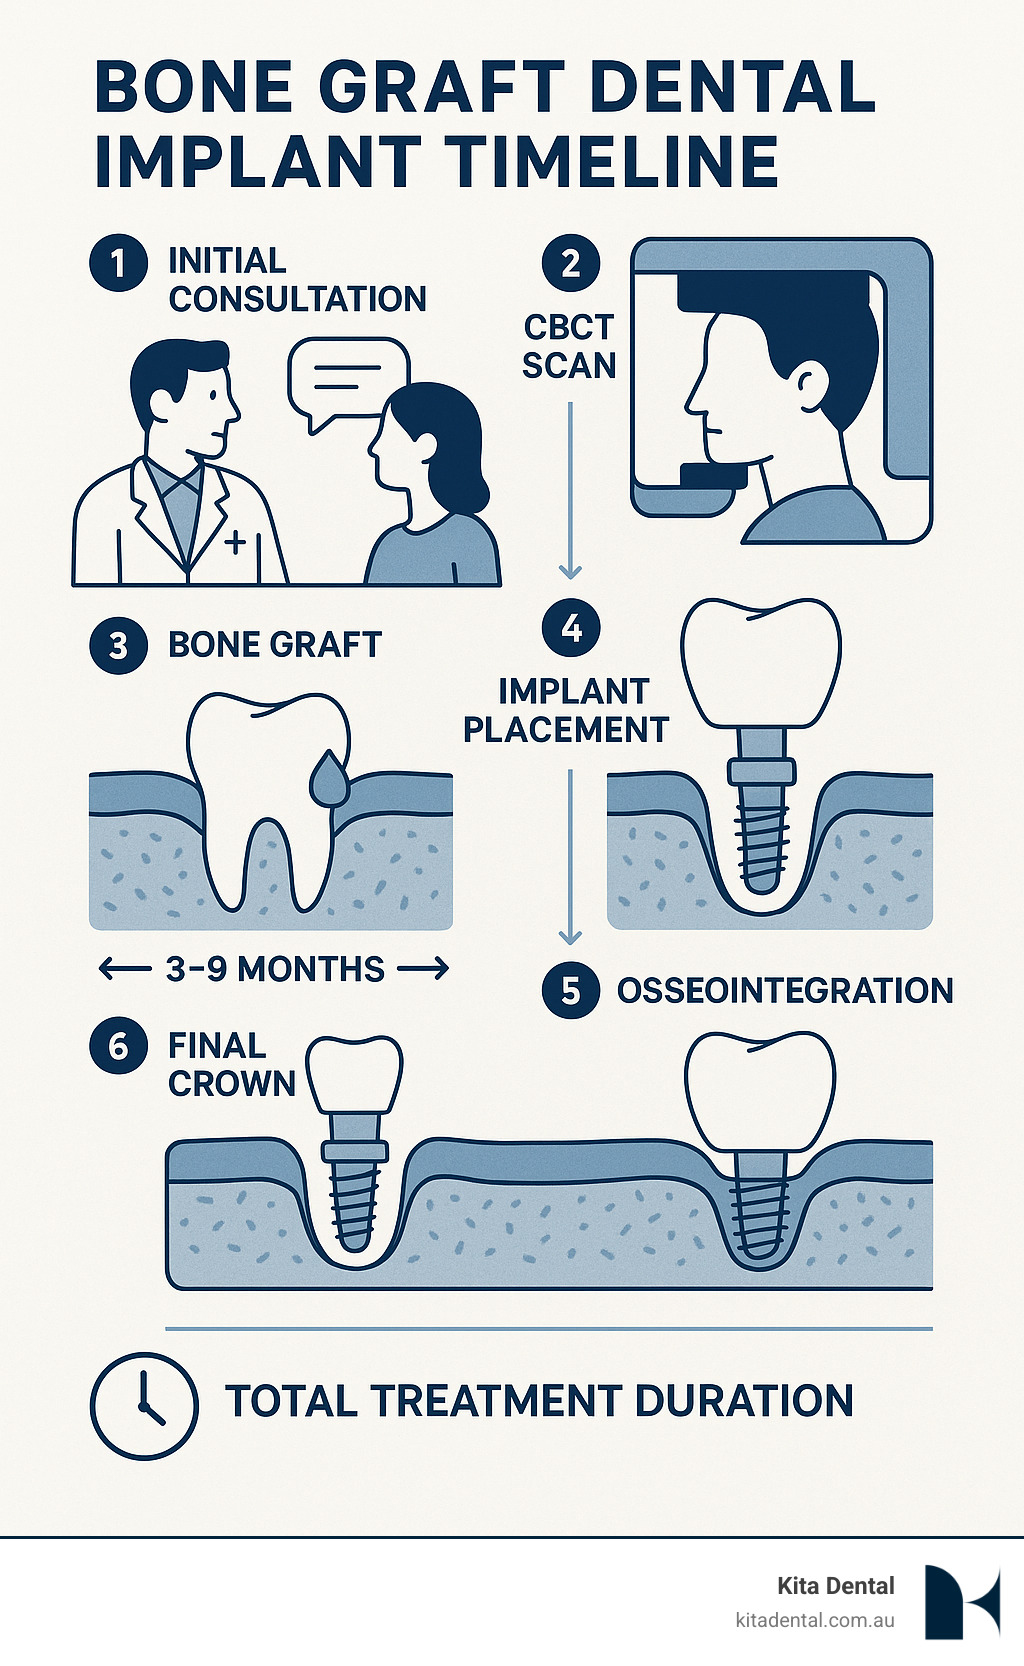

Step-By-Step: Before, During & After Surgery

Knowing exactly what to expect during your bone graft dental implant procedure can transform anxiety into confidence.

Getting Ready: Your Pre-Operative Journey

Your surgical journey begins weeks before the procedure. We’ll take comprehensive CBCT scans that create a detailed three-dimensional map of your jaw. If you take medications like blood thinners, we’ll coordinate with your physician about temporarily adjusting them.

The Surgery Itself: What Actually Happens

Once you’re completely numb and comfortable, we make a small, precise incision to access the bone area. The recipient site gets thoroughly cleaned and prepared. We carefully position and shape the bone material, often placing a protective membrane over the graft. Finally, we close the soft tissues with sutures. The entire procedure typically takes 30-90 minutes.

Healing Timeline & Aftercare

Your bone graft dental implant success depends largely on how well you follow aftercare instructions.

The Critical First Two Days

Ice packs become your best friend – apply them for 20 minutes on, then 20 minutes off. Your diet shifts to soft, nourishing foods like smoothies, soups, and yogurt. Gentle salt-water rinses start after the first day. Sleep with your head liftd on extra pillows.

Week One: Settling In

Continue your soft diet while gradually feeling more normal. Avoid the surgical area when brushing your teeth. We’ll typically see you around day 7-10 to remove sutures and check your healing progress.

Weeks Two Through Four: Getting Back to Normal

Your mouth starts feeling more like itself. You can gradually add more solid foods as comfort allows, but still avoid anything hard, crunchy, or sticky.

The Waiting Game: Months One Through Three

This is where the real magic happens. Your body is actively growing new bone into and around the graft material.

Final Maturation: Months Three Through Nine

Complete bone maturation takes time – typically 4-6 months for most grafts. We’ll take new images to confirm the bone has developed properly before placing your implant.

Your bone graft will take anywhere from 3-9 months to fully mature. Front lower jaw sites typically heal faster – often ready for implant placement in just 3-4 months. Upper back jaw areas may need the full 6-9 months.

The timeline for bone graft dental implant placement varies based on what type of graft you’ve had and how well you heal.

Socket preservation grafts typically need three to four months to mature properly. Small ridge augmentation procedures usually require four to five months. Large block grafts need six to nine months to fully integrate. Sinus lift procedures generally require four to six months of healing time.

Location matters too. Front lower jaw sites often heal faster than upper back areas because of differences in bone density and blood supply. We never rush this process – placing an implant in bone that hasn’t fully matured significantly increases the risk of failure.